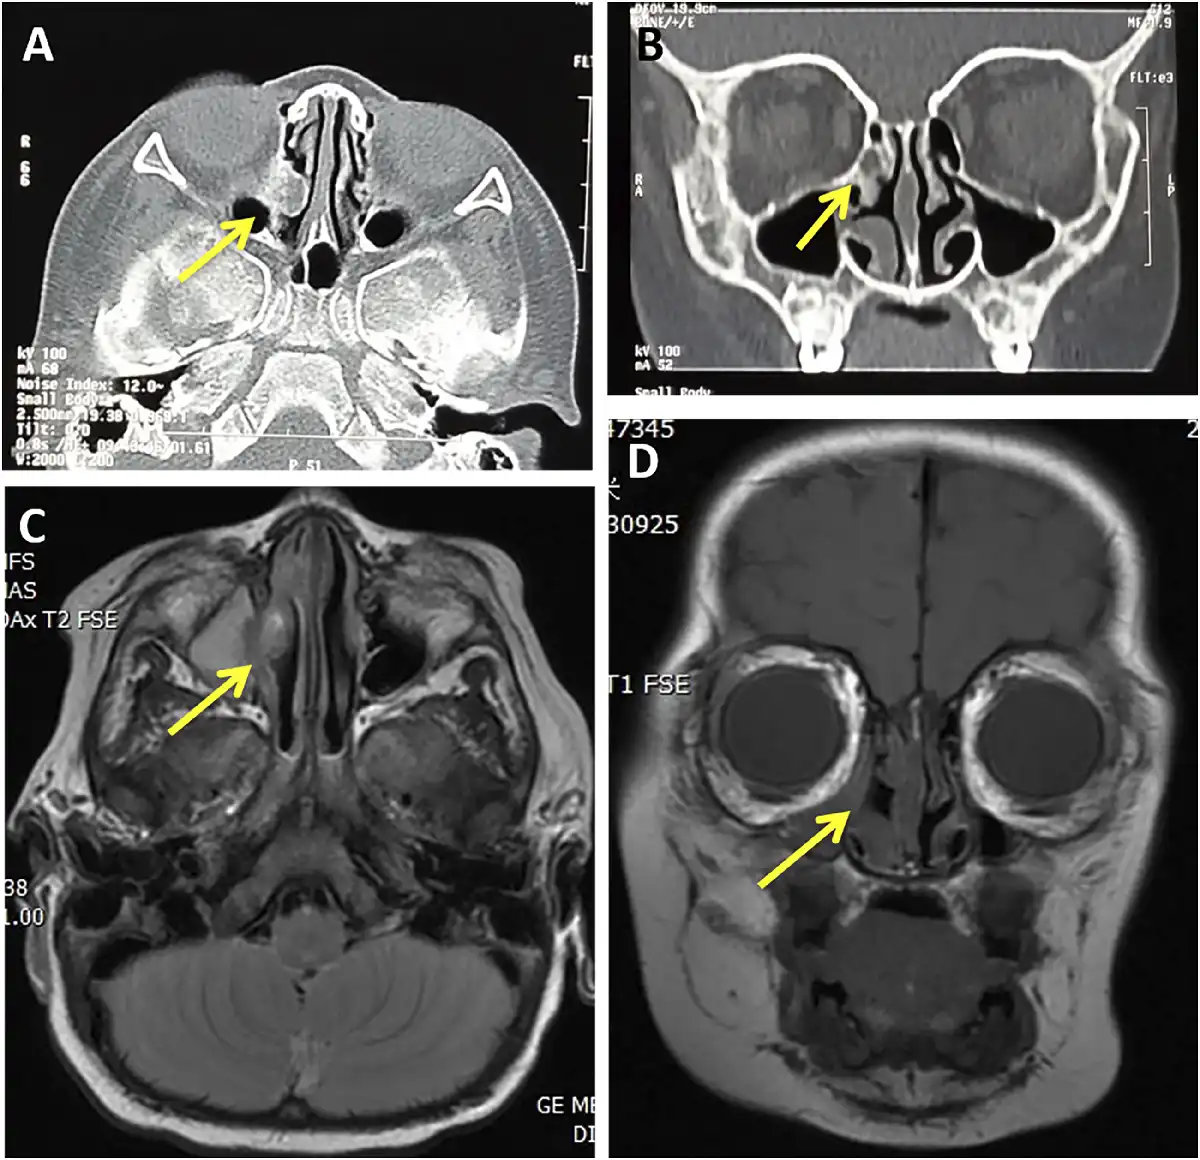

Currently, there is no evidence of recurrence after 1 year since the operation (Figure 3).

Figure 3

The patient’s CT (A, B) and MRI (C, D) of paranasal sinuses after operation: The yellow arrows show the changes in the operative area 1 year after operation: no tumor recurrence, a small amount of local hyperosteogeny and mucosal thickening.